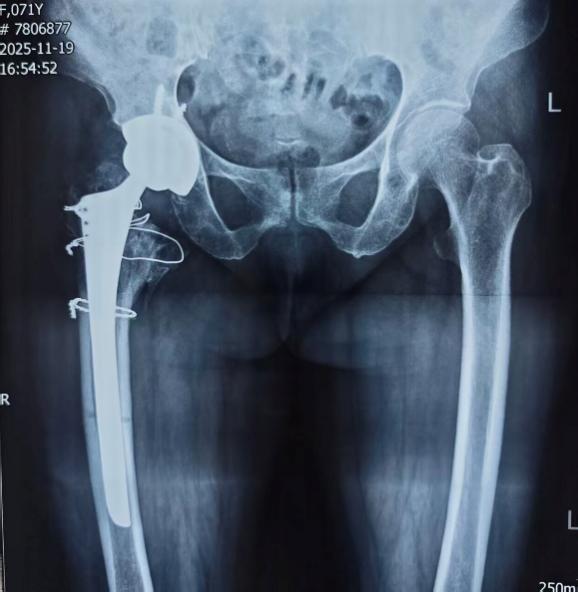

术后X线片

在王争刚主任医师主刀下,手术团队精准取出移位的内固定物,细致处理坏死骨组织,并在骨质缺损区域进行精确重建,最后植入人工髋关节假体。整台手术仅用时1小时,术中出血量少,假体安放位置理想,为患者后续的快速康复奠定了坚实基础。